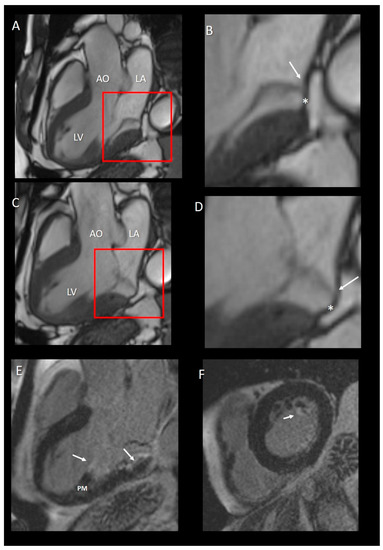

Figure 10.

(A,C) CMR images in long-axis view in diastole (A) and in systole (C). (B,D) Magnified images of the structures in the red squares in panel A and C, respectively. The insertion of posterior leaflets on the atrial myocardium (arrow) is well visible either in diastole (panel B) or in systole (panel C). The asterisks in both B and D panel mark the curtain-like fibrous tissue. (E) Long-axis view late gadolinium enhancement (LGE) showing the fibrosis on the tip of papillary muscle (PM) and at the base of LV (arrows). (F) Short-axis view LGE showing the fibrosis on the tip of PM.